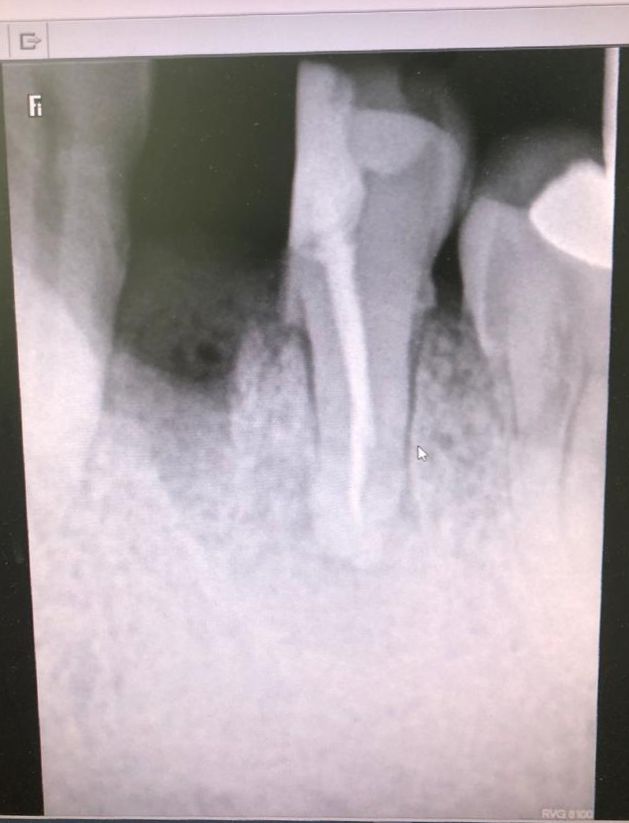

Paciente de mediana edad al que se le hizo una endodoncia con restauración de composite en el primer molar inferior o mandibular izquierdo hace varios años. Con el tiempo ha filtrado haciéndose caries en el interior de la restauración, e incluso en la raíz anterior o Mesial, en la cual se produjo una fractura vertical. Esto provocó el inicio de molestias en el paciente y es cuando acude a la clínica del Doctor Faus. Tras estudio radiológico, y ante el estado y molestias de la pieza, se le propone exodoncia y colocación de implante para restauración definitiva. El paciente con la explicación realizada sobre los implantes dentales manifiesta sus temores y pregunta sobre otras posibilidades menos traumáticas y mas económicas.

Como la raíz del molar que esta con la fractura vertical es la raíz anterior se le explica que hay que separarla de la posterior. A continuación procederíamos a realizar la extracción de ésta y la limpieza de la fibrosis de la zona. Dejamos curar el tiempo necesario para que cicatrice la zona anterior y ver cómo va evolucionando la raíz posterior.